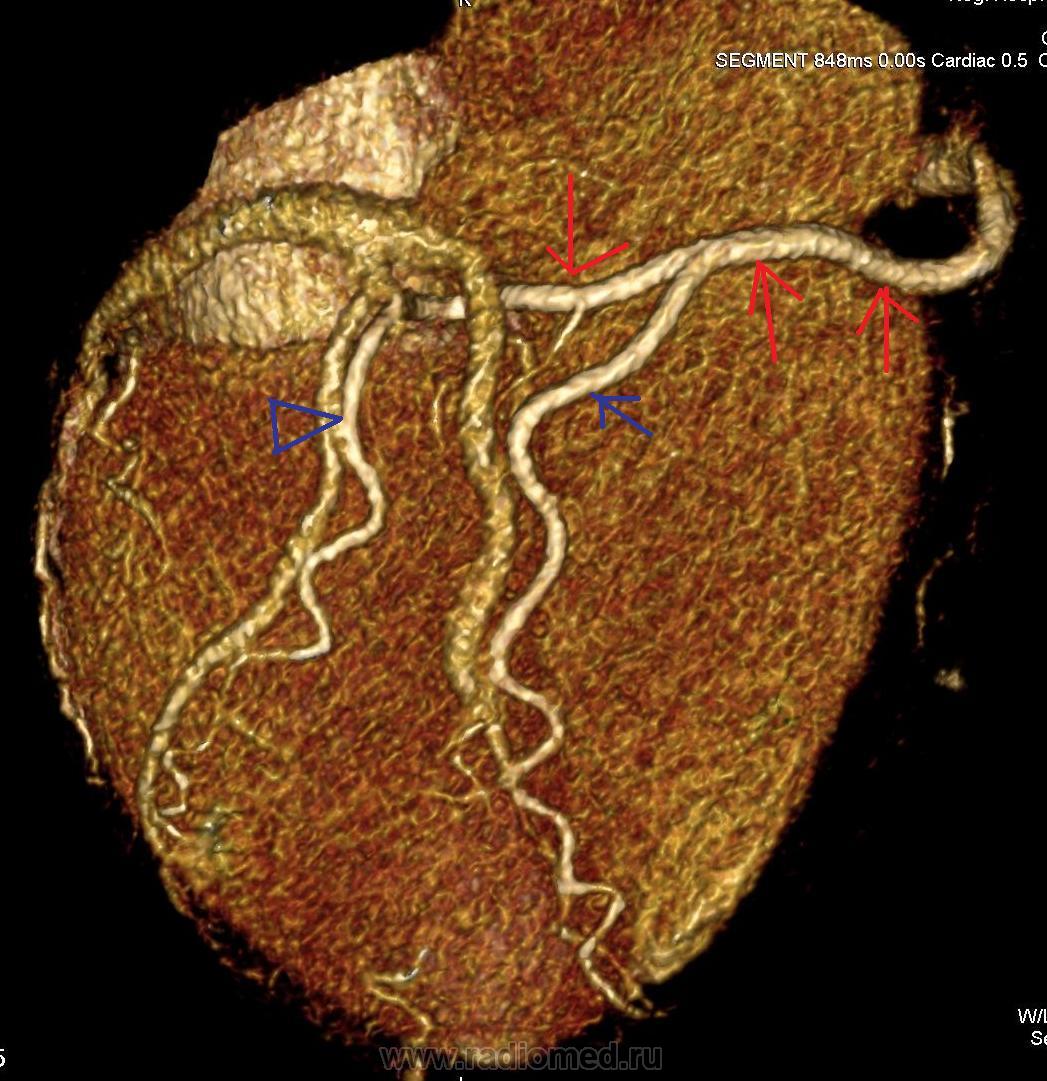

Мы недавно начали проводить КТ-коронарографию. Представляю вариант нормальных сосудов сердца. Довольно типичный вид, тип кровоснабжения преимущественно правый.  Ствол левой коронарной артерии делится на ветви: переднюю нисходящую и огибающую.

Стрелки: Красные - правая коронарная артерия, зеленые - передняя нисходящая, голубые - огибающая артерия, черные - ветвь острого края, желтые стрелки - задняя нисходящая артерия.